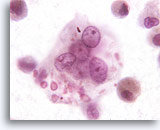

Figure 165

Epithelial Cells

Highly reactive epithelial cells may be seen in patients with pulmonary aspergilloma.

Epithelial Cells

Highly reactive epithelial cells may be seen in patients with pulmonary aspergilloma.

Figure 165

Epithelial Cells

Highly reactive epithelial cells may be seen in patients with pulmonary aspergilloma.

Epithelial Cells

Highly reactive epithelial cells may be seen in patients with pulmonary aspergilloma.